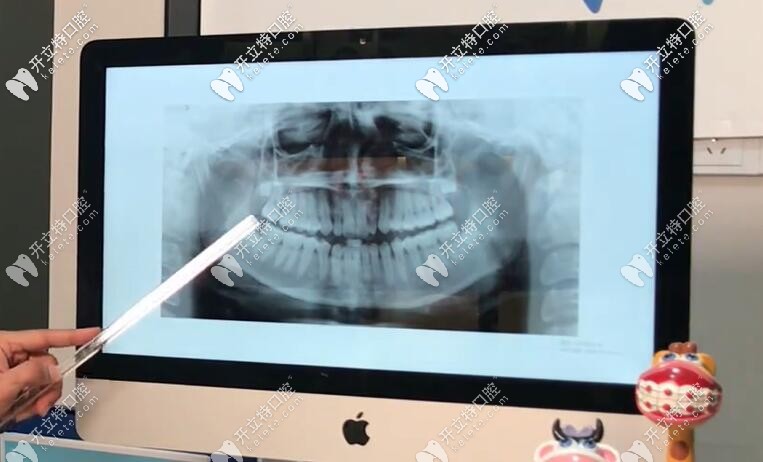

【基本情況】:從圖中(正面)我們可以看出,這個姑娘的下巴有一點(diǎn)歪,但是她的中線上頜還不錯,可是出下巴這邊,她的咬合是不對的,上下頜各有兩顆智齒;

通過x片和國貿(mào)口腔的正畸技術(shù)總監(jiān)Dr.Aref安粵夫的分析后,發(fā)現(xiàn)她有點(diǎn)骨性三類牙齒畸形,她的下巴有點(diǎn)長,地包天牙齒有骨性問題。